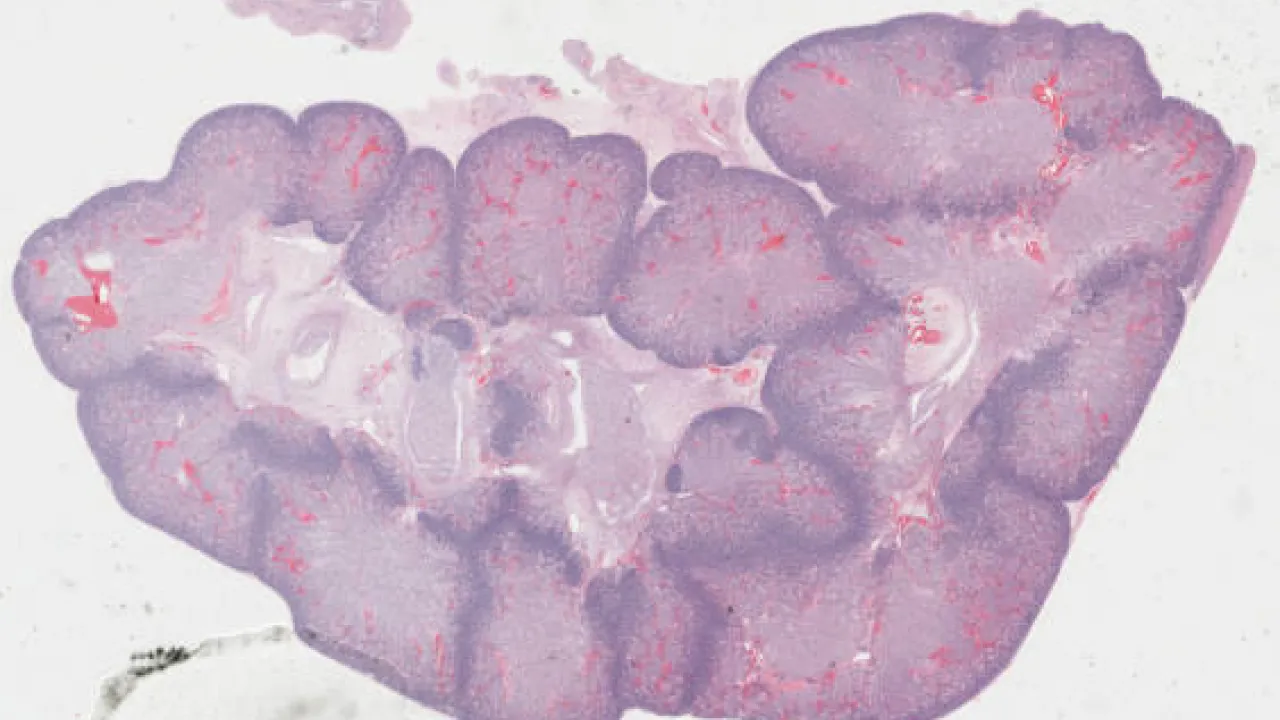

Kidney, Papillary renal cell carcinoma